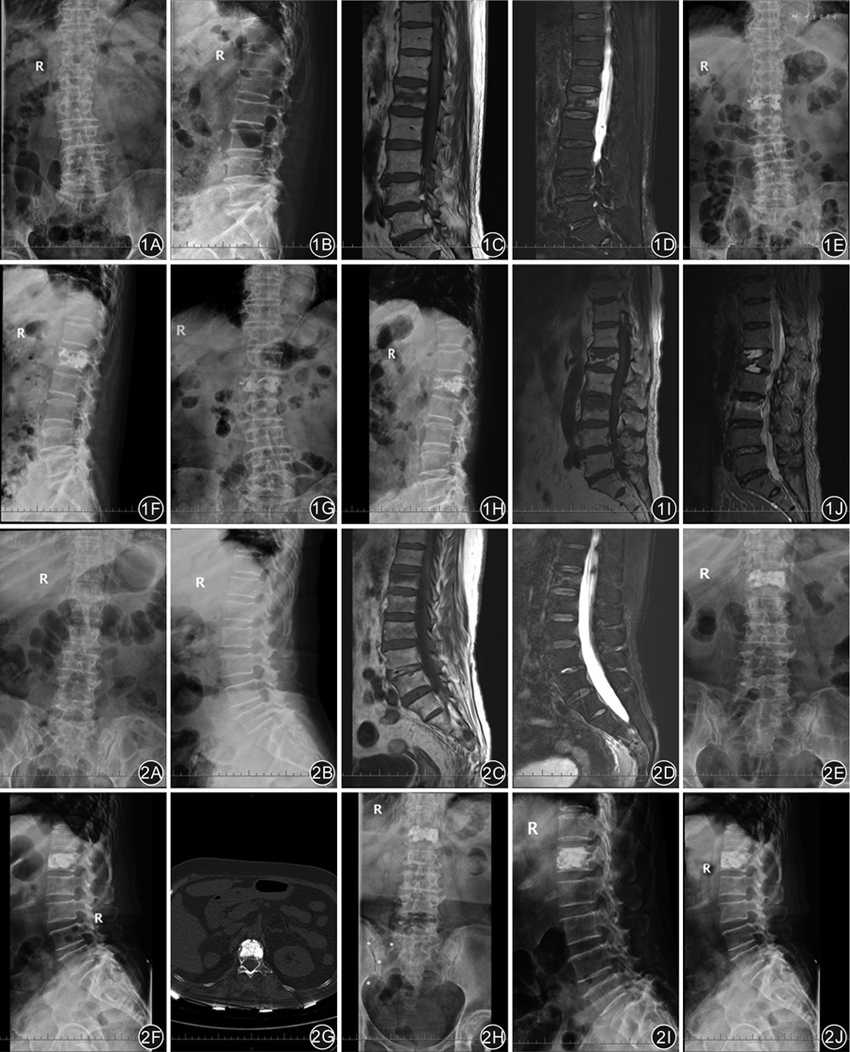

2组患者均随访1年。随访期间,良好组出现3例(2.9%)邻近椎体骨折、8例(7.6%)椎体高度丢失、6例(5.7%)残余痛;其中邻近椎体骨折有1例行PVP、1例行皮椎体后凸成形术(percutaneous kyphoplasty,PKP)、1例保守治疗,6例残余痛均行保守治疗。骨水泥分布欠佳组出现11例(9.7%)邻近椎体骨折、20例(17.7%)椎体高度丢失、18例(15.9%)残余痛,11例邻近椎体骨折者中6例行PVP、3例行PKP、2例保守治疗,18例残余痛均行保守治疗。良好组术后1年邻近椎体骨折、椎体高度丢失、残余痛发生率均低于欠佳组,差异均有统计学意义(χ2=4.28、4.94、5.80,P值均<0.05)。典型病例见图1、2。

组内比较:2组患者术后第1天与术前比较,VAS评分、ODI及Cobb角均减少,AVH、PVH均增大,差异均有统计学意义(P值均<0.001)。2组患者术后1年与术后第1天比较,良好组VAS 评分、ODI、Cobb角及AVH、PVH差异均无统计学意义(P值均>0.05);欠佳组VAS 评分、ODI及Cobb角均增大,AVH、PVH均减小,差异均有统计学意义(P值均<0.001)。2组术后1年骨密度与术前比较,差异均有统计学意义(P值均<0.001)。见表2。

组间比较:2组患者术前及术后第1天比较,VAS评分、ODI、Cobb角、AVH、PVH组间比较,差异均无统计学意义(P值均>0.05)。良好组术后1年VAS 评分、ODI、Cobb角均小于欠佳组,AVH、PVH均大于欠佳组,差异均有统计学意义(P值均<0.05);术前和术后1年的骨密度差异均无统计学意义(P值均>0.05)。见表2。

PVP术中骨水泥注入椎体可与周围骨松质紧密固定,能有效稳定术椎的高度及维持伤椎的稳定。骨水泥的生物力学强度和稳定性与其分布状态密切相关,在长期应力作用下可导致术椎的生物力学发生改变。分布良好的骨水泥可与骨小梁紧密铆合,大大增加术椎的力学稳定性[12];而骨水泥分布欠佳会加大载荷传递阻力,使术椎无法获得理想的力学支撑。由于骨水泥的刚度与硬度明显高于正常的椎体组织,而未填充局部区域骨质相对脆弱,易受应力集中压缩及异常传导。因此,骨水泥分布欠佳会影响术椎的刚度、强度及生物力学分布[13],导致术椎高度丢失及邻近椎体骨折,可加重疼痛和导致后凸畸形,严重时甚至需翻修手术治疗[14],进而影响远期疗效。本研究结果显示,2组患者术后第1天的Cobb角、AVH、PVH均较术前改善,且2组间差异无统计学意义,提示PVP治疗有效;术后1年骨水泥分布良好组AVH、PVH均大于欠佳组,而VAS评分、ODI、Cobb角及椎体高度丢失、邻近椎体骨折、残余痛发生率均低于欠佳组,提示骨水泥分布良好组疗效优于欠佳组,与上述既往文献报道相似。近期还有研究报道,OVCFs患者远期治疗的核心是抗骨质疏松症治疗[15],以降低椎体高度丢失及邻近椎体骨折的风险。本研究发现,经过抗骨质疏松治疗,2组术后1年的骨密度较术前明显改善;但随访期间骨水泥分布欠佳组仍出现11例邻近椎体骨折及20例椎体高度丢失,发生率明显高于良好组。笔者分析原因,可能是为术后活动时,分布欠佳的骨水泥引起应力集中效应,导致椎体内的微骨折和椎体高度的进行性丢失,甚至导致骨水泥与骨小梁接触面失衡,出现术椎塌陷及后凸畸形等[16]。因此,骨水泥分布状态可能是影响PVP术后疗效的关键因素之一。